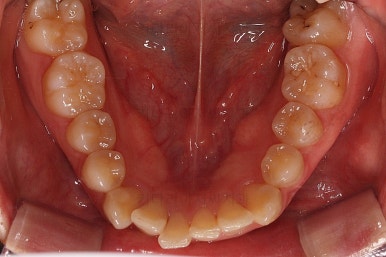

마찬가지로 부산연산동교정치과 초진 시 입안의 모습입니다.

눈에 띄는 것은 윗니 안쪽 치아 하나가 아예 입천장쪽으로 나서 매우 삐뚤어요.

저렇게 삼각혁으로 배치되어 있는 치아는 셋 중 하나는 꼭 썩어요.

셋 사이에 음식물이 잘 끼고 양치가 힘들기 때문이죠.

아래 앞니도 삐뚤한 편이었고 아래 앞니가 불쑥 위로 올라와 있어서 이를 악 다물면 위아래 앞니가 많이 겹치는 "과개교합" 패턴이 나타나요.

윗니가 전반적으로 아랫니보다 앞에 나와 있어서 2급 부정교합에 윗니만 튀어나온 양상이고 이 때문에 윗니 앞니가 다치고 부러졌따가 떼운 흔적이 보이네요.